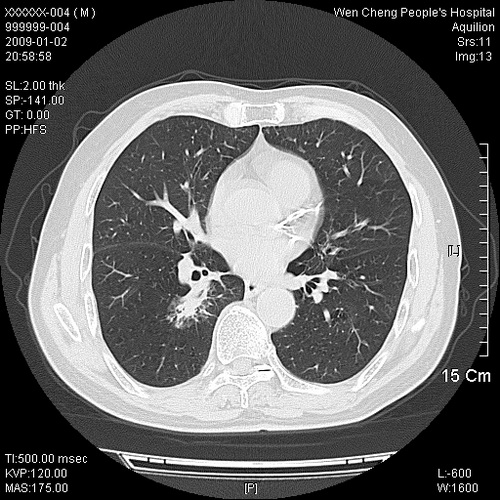

男性,73岁,有慢支病史,肿瘤系列标志物检验正常,血沉及血常规正常

右肺下叶背段小片状 磨玻璃样模糊影,内见血管及含气支气管像,支气管管壁增厚。考虑:慢性炎症!

右肺下叶背段小片状 实性与磨玻璃样影,内见血管及含气支气管像,支气管管壁增厚,边缘见长毛刺影。考虑:慢性炎症或肿瘤!建议抗炎治疗复查,密切观察随访!

右肺下叶片团状影内见扩张的含气支气管和支气管管壁增厚,其周有磨玻璃样模糊影和长毛刺。考虑慢性炎症可能性大。

2、右肺下叶片团状影内见扩张的含气支气管和支气管管壁增厚,其周有磨玻璃样模糊影和长毛刺。考虑周围型肺ca可能,结核不排。

高度提示细支气管肺泡癌,建议抗炎治疗半月观察病灶变化,如无明显改变,建议立即手术治疗.